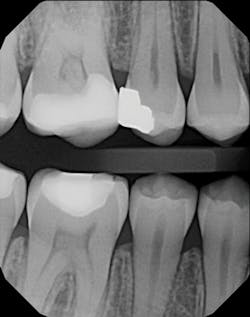

DX Platinum VBW x-ray

Digital x-rays brought us instant images and used no chemicals or film. They eliminated costs and messes. Digital images now provide an interface between me and my patients. I can instantly display images on a 32-inch screen above the chair for patients to see. In my opinion, this instant view is invaluable when doing implants or endodontics. It’s a substantial time-saver. I can enlarge, manipulate, colorize, and draw on these images, which contributes to patients’ understanding of their dental problems. Some patients don’t want to know their problems! But if I can see the problems clearly, I also can identify an appropriate solution and communicate it to them. This type of involvement can lead patients to accepting treatment that is in their best interest and ultimately helps build my reputation as a responsible, caring dentist.